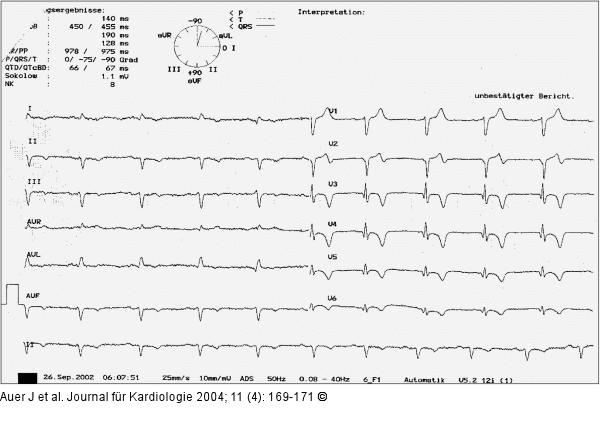

Abbildung 7: Akutes Koronarsyndrom - Stenose der linken Herzkranzarterie EKG 30 Minuten nach pharmakologischer Stabilisierung des klinischen Zustandes und Abklingen der Thoraxschmerzen |

Abbildung 7: Akutes Koronarsyndrom - Stenose der linken Herzkranzarterie

EKG 30 Minuten nach pharmakologischer Stabilisierung des klinischen Zustandes und Abklingen der Thoraxschmerzen |